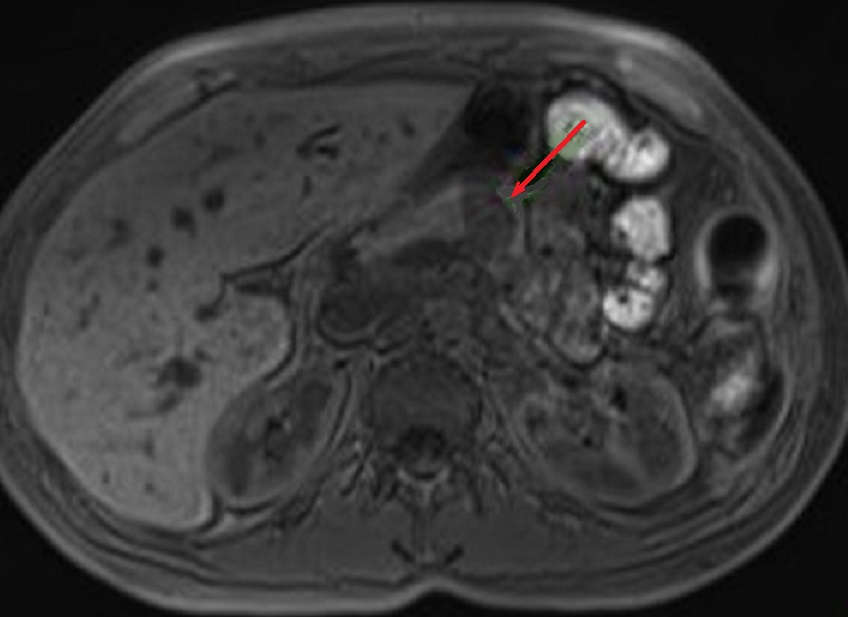

L'IRM : C'est technique

avait une sensibilite resemble la TDM . Aspect radiologique

IRM d'une tumeur endocrine du pancreas est image hypointense

sur T1 ( relative avec parenchyme du pancreas ) et

hyperintense sur les coupes pondere T2 . Sur les coupes T1

avec Gadolinium intraveineuse ( Gd ) le tumeur est

hypervascularise et hypersignal .

Aspect lesionnel d'une

tumeur endocrine du pancreasest image hyposignal

T1 ( fleche rouge ) . Image radiologique IRM

T1 d'une tumeur endocrine du corp pancreas en coupe

axiale . |

Meme cas en coupe IRM ponderation T2 (

fleche rouge . La tumeur devient hypersignal que le

parenchyme du pancreas . Ce que se donne comme une

technique d'utilise pour decouverte des petites

tumeurs |